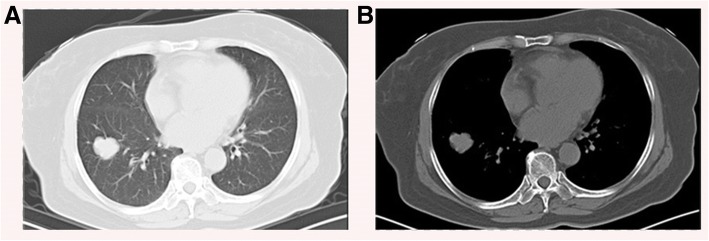

A 65-year-old female presents to clinic with 1 week cough. She denies fever, dyspnea, chest pain or constitutional symptoms. She had a history of type II diabetes but with an inadequate controlled serum glucose level for 10 years. Her neutrophils, C-reaction protein (CRP), procalcitonin and tumor markers such as carcinoembryonic antigen (CEA), neuron-specific enolase (NSE), squamous cell carcinoma antigen (SCC) were all in normal range. Her T-SPOT.TB assay examination were negative. A CT scan of her chest reveals a 25–29 mm, round-like, heterogeneous lobulated solitary pulmonary nodule without showing any cavity lesions or calcification, in the peripheral right lower lobe. No obvious enlarged hilar or mediastinal lymph nodes were observed (Fig. 1). Preoperative brain magnetic resonance imaging (MRI) scans showed negative findings. The patient hadn’t received PET/CT scan for economic reasons.

Fig. 1.

Chest CT scan showing a nodule in the right lower lung field. a Lung window. b Mediastinal window